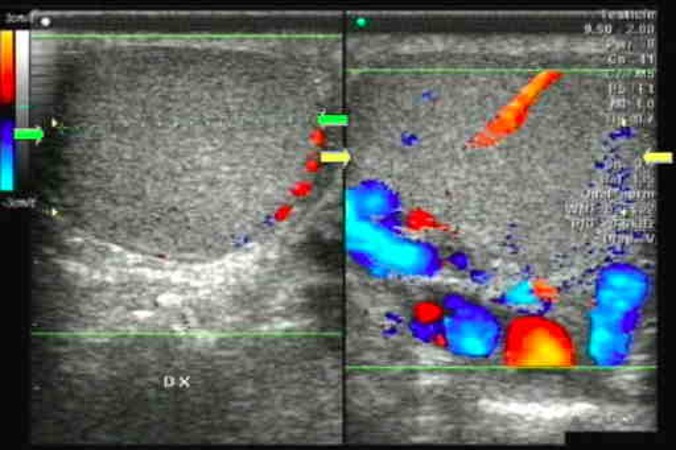

I TESTICOLI

Sono organi pari di forma ovale, di dimensioni variabili con l’età (nell’adulto il diametro longitudinale è 4-4.5 cm, il volume 15-20 mL), situati in sede extra-addominale nella borsa scrotale e sospesi al funicolo, che li collega alla parete addominale attraverso il canale inguinale. Sul polo posteriore si trova l’ilo testicolare, attraverso il quale passano i dotti efferenti e le strutture vasculo-nervose convogliate poi dal funicolo (2). Il polo inferiore è ancorato in basso da un legamento fibroso, che è il residuo del gubernaculum, mentre sul polo superiore si adagia la testa dell’epididimo.

Nel funicolo decorrono tre arterie che assicurano l’irrorazione arteriosa del testicolo:

- l’arteria testicolare, che origina dall’aorta;

- l’arteria deferenziale, ramo della vescico-deferenziale, che origina dall’arteria iliaca interna;

- l’arteria cremasterica, ramo dell’epigastrica inferiore, derivante dall’iliaca esterna.

Il drenaggio venoso avviene attraverso i plessi pampiniforme anteriore e posteriore dello scroto, che confluiscono nelle vene spermatiche:

- la vena spermatica interna drena nella vena epigastrica omolaterale;

- la vena spermatica esterna drena a destra direttamente nella cava e, a sinistra, nella vena renale omolaterale.